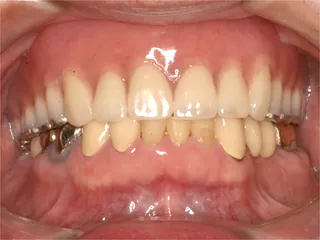

治療前 治療前

ハイブリッドレジン冠・治療後 治療後

強化プラスチックの被せ物で金属を使用していません